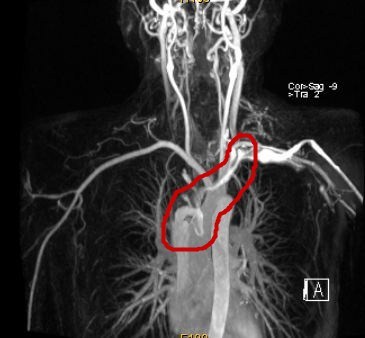

肿瘤侵犯上腔静脉,导致上腔静脉消失在影像中

钱有辉教授团队立即为张先生安排了更为详细的全身检查,发现肿瘤将近10cm大小,已经侵犯上腔静脉,上腔静脉、双侧头臂静脉及右侧颈内静脉内已经有癌栓并血栓形成,上腔静脉已经无法通过影像看到,正是这些栓子导致张先生出现了头晕、脸肿等上腔静脉阻塞的症状。钱有辉教授仔细分析病情后指出:"本例患者主要问题在于患者的胸腺瘤已经出现了大血管侵犯,手术需要完整切除肿瘤之外还需要对部分大血管进行切除并置换人工血管,这样才能达到斩草除根的效果"

(肿瘤阻塞了上腔静脉,血流受阻,造影不能显现)